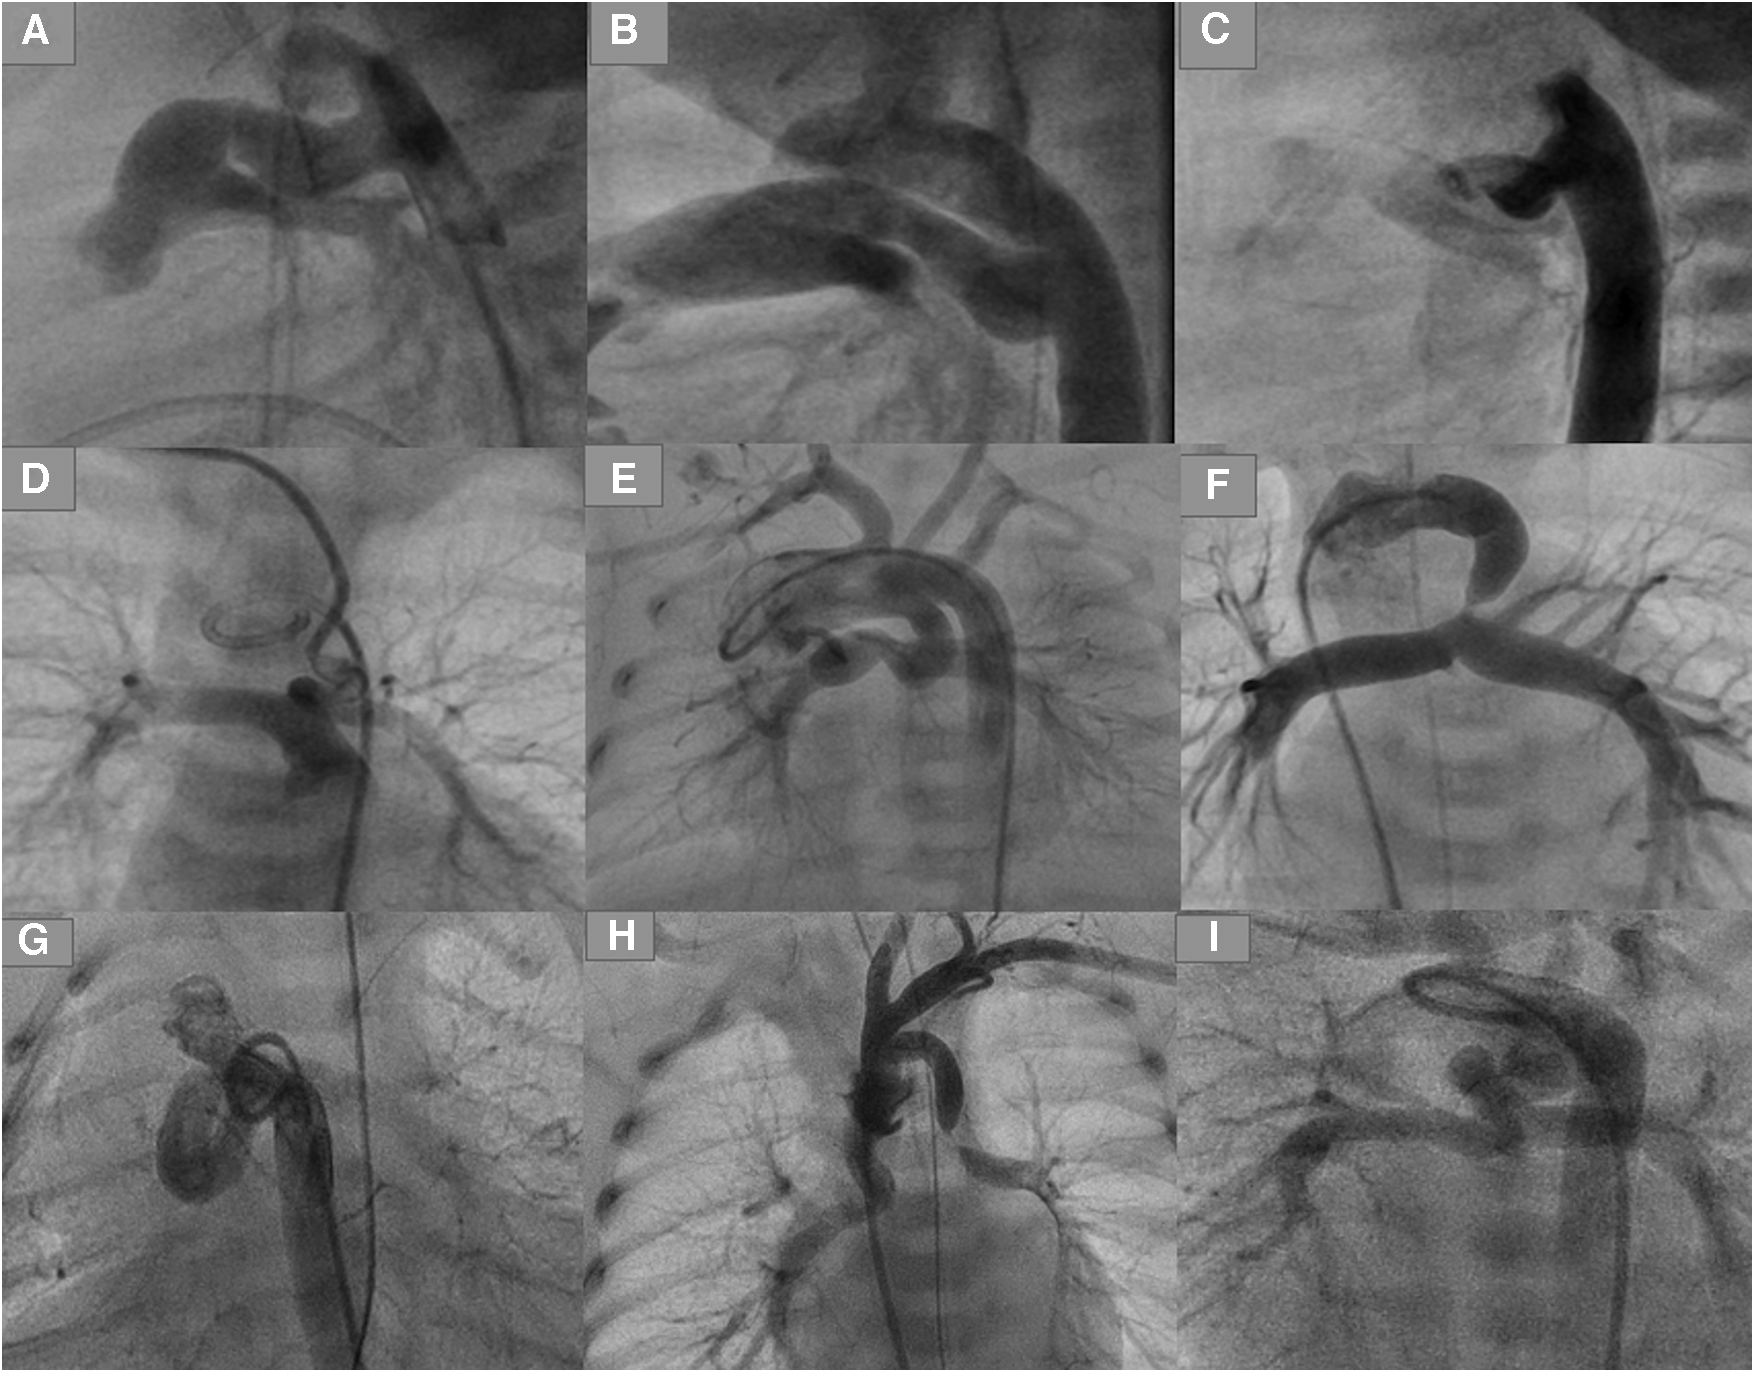

Figure 1

Types of ducts in congenital heart disease with duct-dependent pulmonary circulation. (A,B) Typical ducts originate from DAO in PA-IVS. (C) Tortuous duct originates from DAO with multiple complex curves. (D,E) Ducts originate from aortic arch with cervical course. (F) Duct originates from left subclavian artery. (G) Tortuous duct originates from DAO proximal to aortic arch. (H) Double ducts, the first originates from left subclavian artery and the second from the aortic arch. (I) Tortuous duct originates from aortic arch with multiple complex curves.